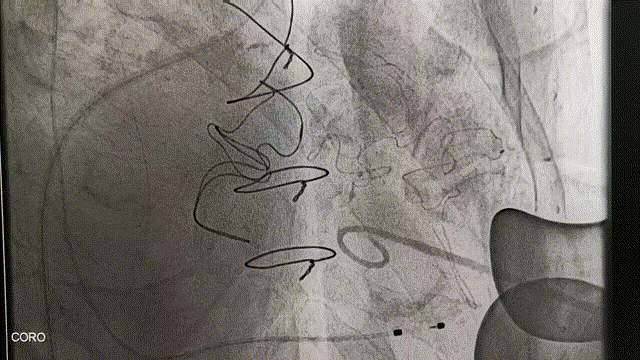

冠脉造影:左主干未见明显狭窄,前降支未见明显狭窄,血流TIMI3级,回旋支中段约40%狭窄,血流TIMI3级,右冠状动脉中段远段闭塞,血流TIMI0级。

DSA引导下定位心尖,心尖穿刺后置入泥鳅导丝及导管。利用导丝导管配合,穿过二尖瓣生物瓣。通过二尖瓣后置换加硬导丝。沿加硬导丝,置入J-Valve植入器。术中,通过观察定位件跳动的形态判断瓣膜位置,同时可以清晰感觉到力的反馈。定位件稳稳锚定原瓣架,可看到三个定位件随着心脏搏动而自然摆动。确定好位置后释放瓣膜,锁丝脱钩,瓣膜与植入器完全分离。观察瓣周漏与瓣膜形态,经食管超声心动图显示瓣膜位置合适,形态良好,无瓣周漏和反流。